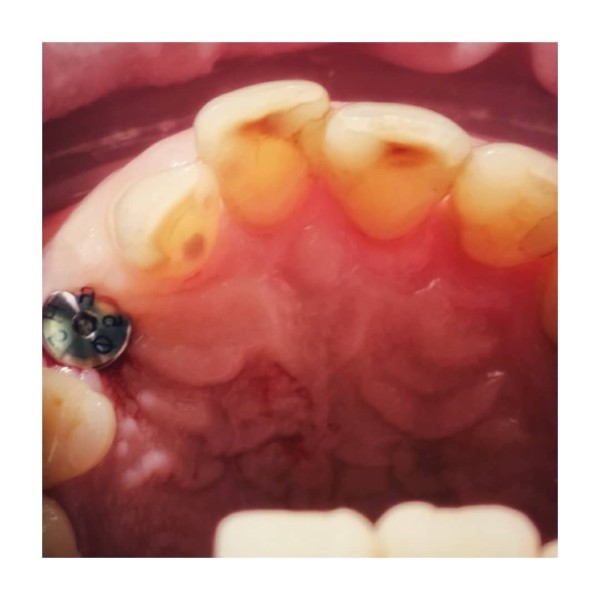

Implantoprotetyka. Lekarz odkręca śrubę gojącą, a na jej miejsce wprowadza specjalny przenośnik. Następnie zostaje pobrany bardzo dokładny wycisk masami protetycznymi.

Cementowanie lub przykręcenie gotowej pracy protetycznej na implancie.